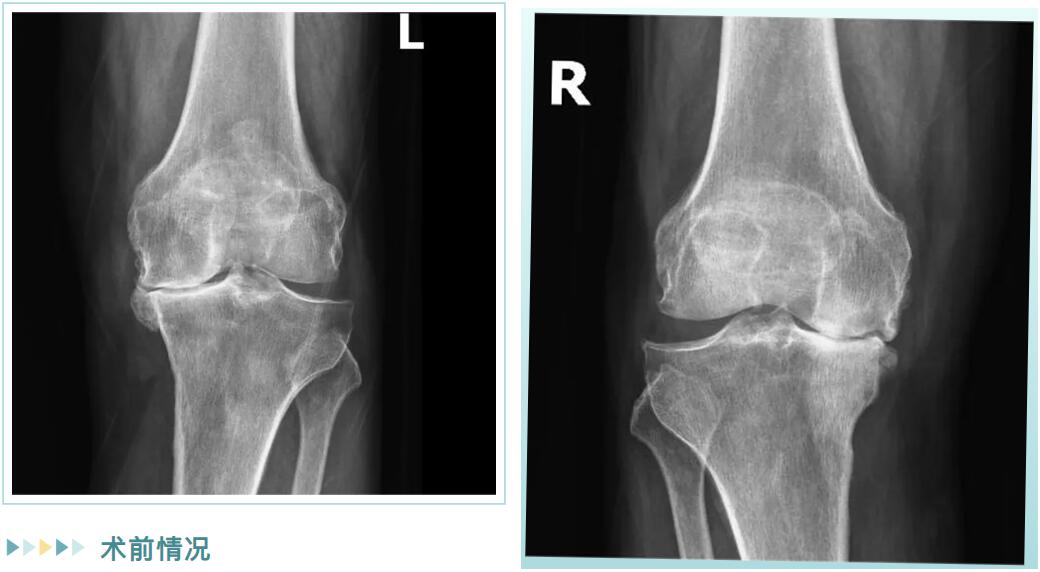

经详细检查,邵阿伯被诊断为“双膝重度骨性关节炎”。在保守治疗无效后,罗院长团队为他量身定制了治疗方案:双侧膝关节内侧单髁置换术。

术前情况